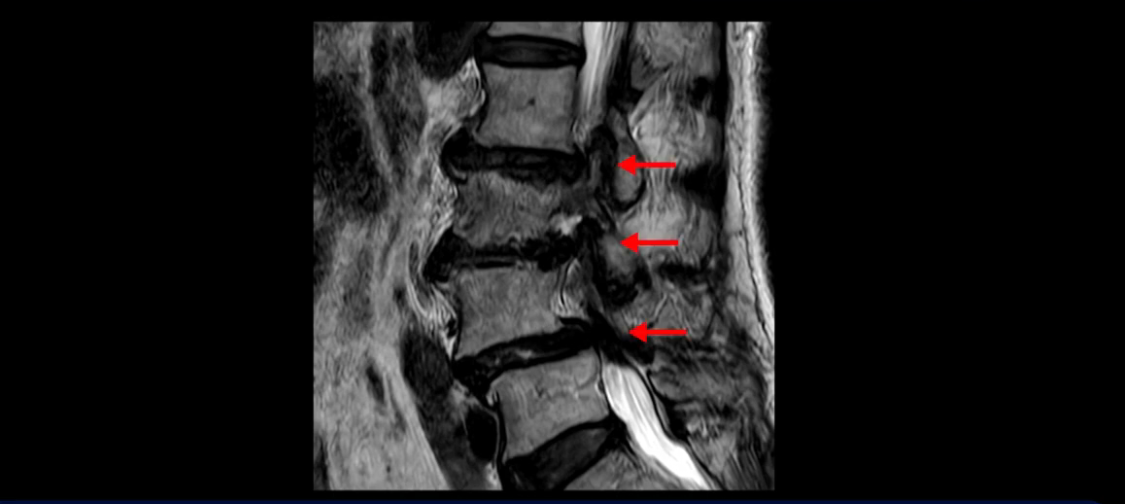

먼저 이분 MRI를 보고 자세히 설명해 드린 후 어떻게 허리 여러 마디에서 협착과 전방전위로 신경이 심하게 눌려 보이는 환자가 수술 없이 좋아질 수 있는지, 또 치료는 어떻게 하는지 설명해 드리겠습니다.

이분 MRI 보시면 허리 3마디의 퇴행이 매우 심합니다.

4번 5번에는 뼈가 밀려 나간 전방전위증도 있고,

또 척추관협착도 매우 심합니다.

척추관이 심하게 좁아져 있습니다.

이렇게 여러 마디가 안 좋고 뼈도 밀려 나가 있으니까 나사박는 수술해야 하는데, 대학병원에서도 수술을 한 번에 못 하고 두 번에 나눠서 해야 한다고 들으셨습니다. 왼쪽으로 신경가지가 빠져나가는 추간공도 많이 좁아져 있습니다.

이렇게 신경 구멍들이 좁아져 있고 신경이 눌리니까 엉덩이와 다리가 너무 저리고 아파서 아예 일어서질 못하니까 휠체어를 타고 병원에 내원하셨는데요. 그럼 어떻게 이분처럼 신경이 눌려있는 환자분들을 수술 없이 치료해서 잘 걷게 만들고 엉덩이와 다리가 저리고 아픈 증상이 사라지게 할까요? 지금부터 설명해 드립니다.